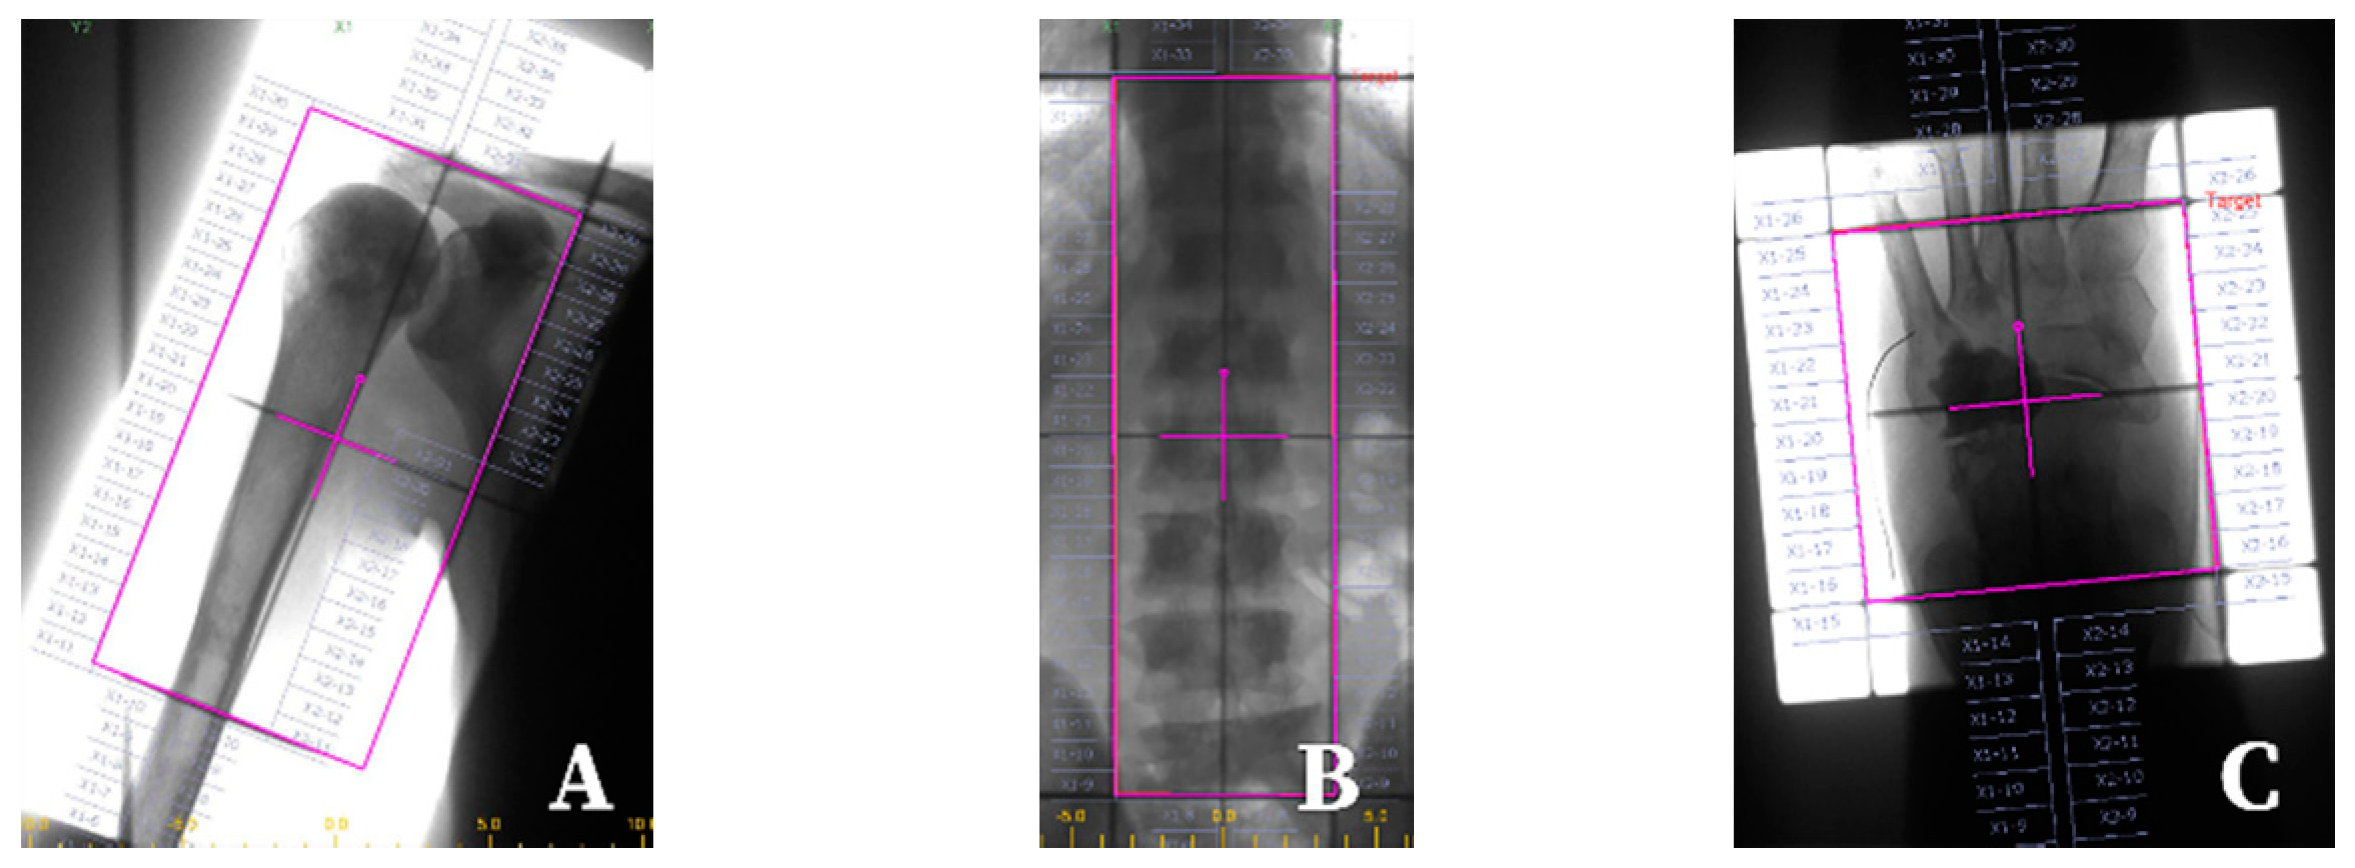

- Li, T.; Li, J.; Wang, Z.; Liu, B.; Han, D.; Wang, P. A preliminary comparative clinical study of vertebroplasty with multineedle or single-needle interstitial implantation of 125I seeds in the treatment of osteolytic metastatic vertebral tumors. J. Neurosurg. Spine 2014, 20, 430–435. [Google Scholar] [CrossRef] [PubMed]

- Qian, J.; Bao, Z.; Zou, J.; Yang, H. Effect of pedicle fixation combined with 125I seed implantation for metastatic thoracolumbar tumors. J. Pain Res. 2016, 9, 271–278. [Google Scholar] [PubMed]